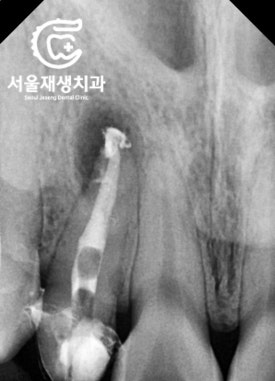

재신경치료 시작~

![[재신경치료] 소중한 내 앞니...재신경치료로 다시 한 번 살려 쓸 수 있습니다. (서울재생치과, 현미경신경치료) 관련 이미지 6](https://pub-9f2bb3498faf4d1d8714b41df24753e3.r2.dev/content/clinics/archive/nqmm0udu86/naver_blog/honeybeevuvu/assets/by_hash/0bdf9fa07c11931031abc444d2776f69fd2a6abdd78f71edae95f91567e69a2f.jpg)

이전 치료에서 포스트

(=뿌리와 머리를 연결해주는 지지대)가

있었지만,

어렵지 않게 제거하고

뿌리 끝까지 꼼꼼히 청소하였습니다.